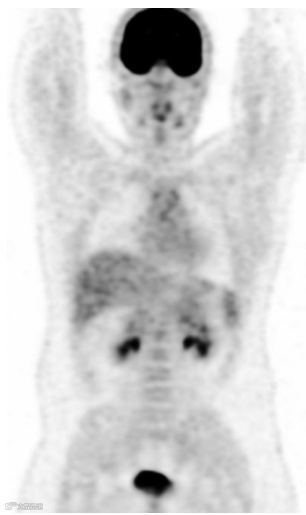

图1. 冠状18F FDG PET 扫描显示脑、心脏、肝脏、脾脏、尿液收集系统(包括膀胱)和骨髓的生理18F FDG 摄取正常。请注意,与身体其他部位的摄取相比,脑部的摄取明显强烈。

FDG在体内的正常生理积累基于葡萄糖代谢,而葡萄糖代谢是可变的。生理摄取通常可见于脑、心脏、肝、脾、胃肠道、泌尿集合系统(包括膀胱)和骨髓(图1)。